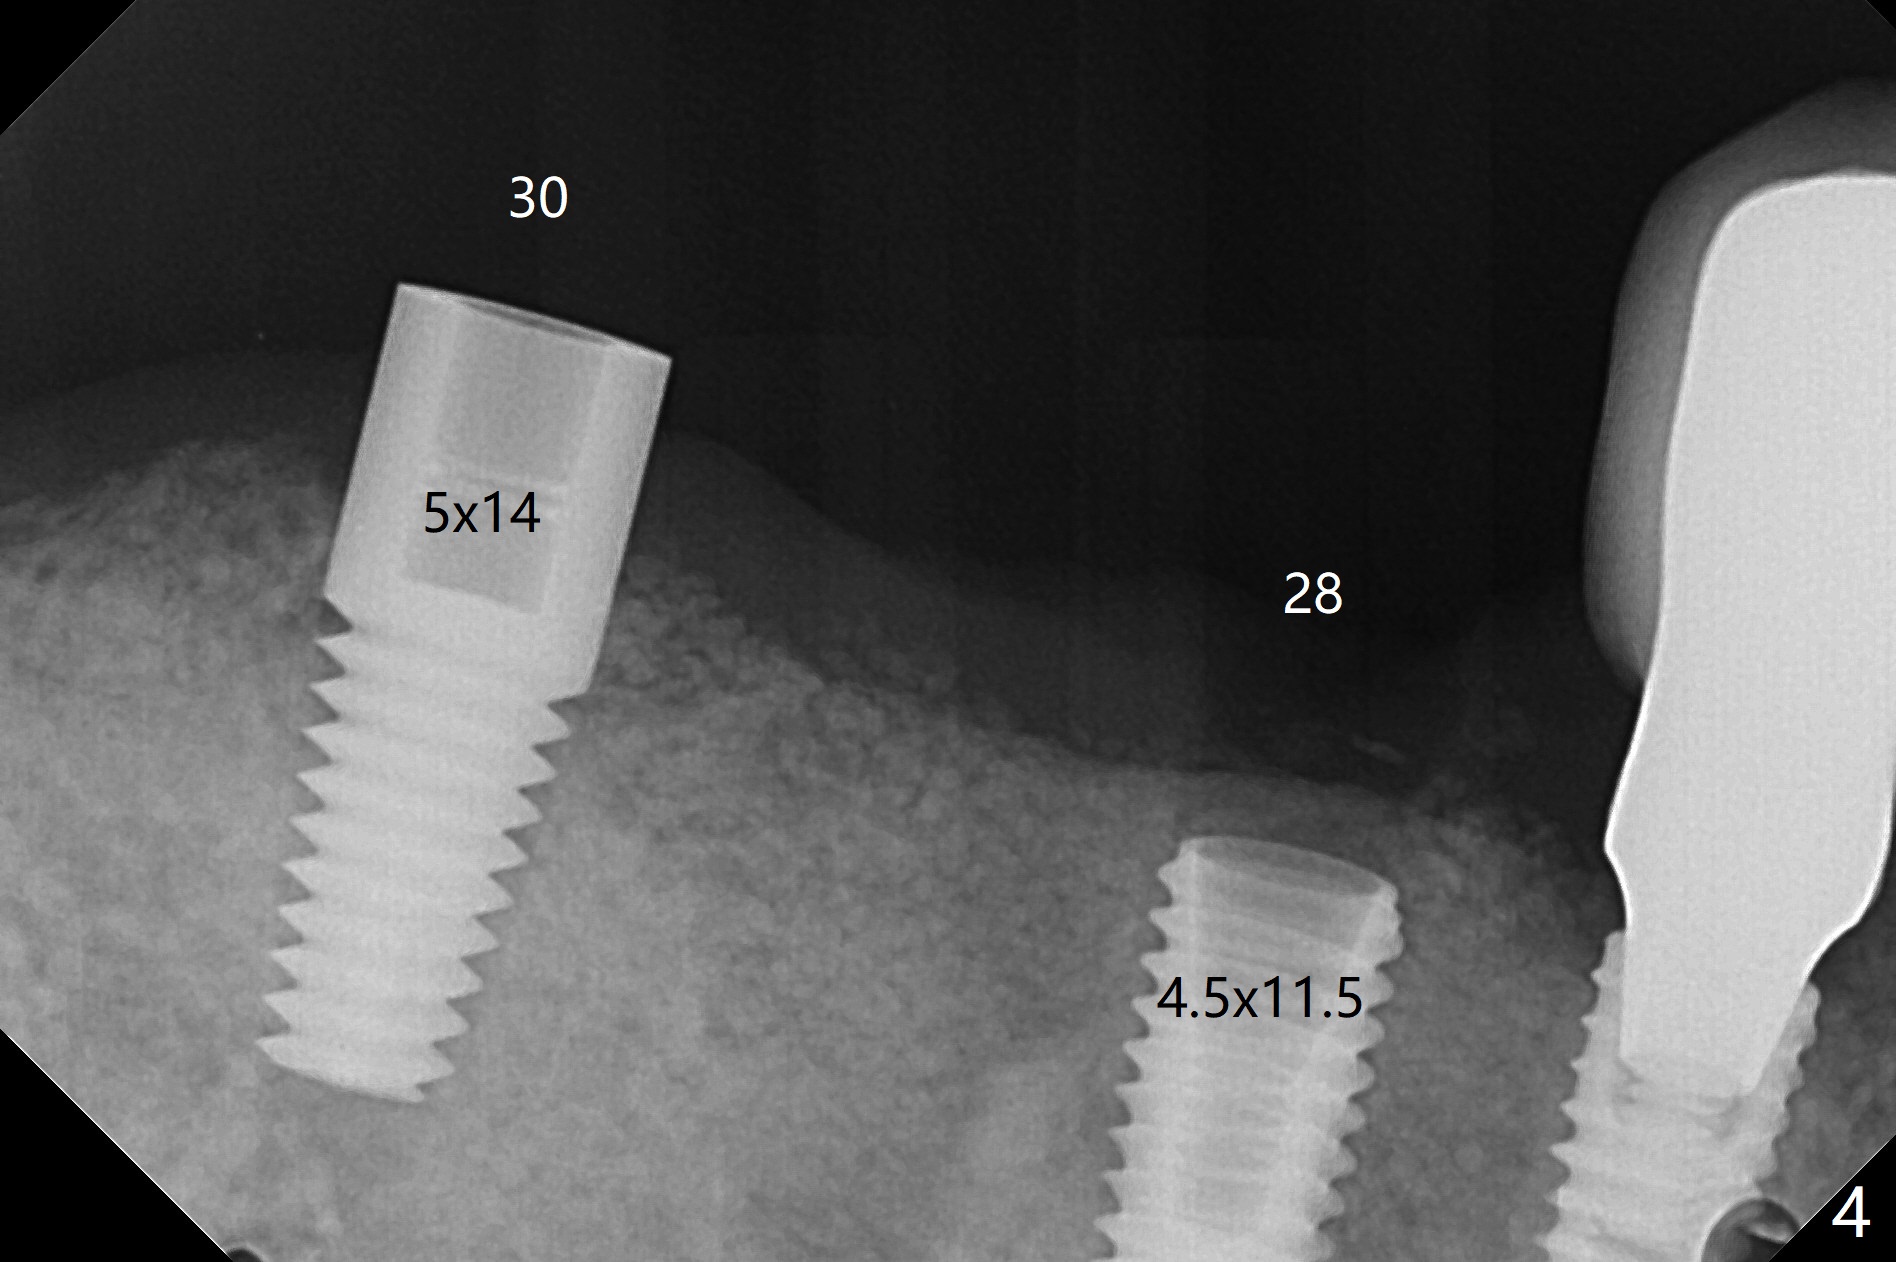

The ridge post bone graft (#28) and socket preservation (#30) is wide. Using a surgical guide (Fig.2), tissue punch is used to initiate osteotomy without compromising the keratinized gingiva (Fig.3). With no stop fixture mount for a 4.5x11.5 mm implant being placed at #28, the osteotomy at #30 is much easier. A 5x17 mm Tatum tapered tap is inserted with the guide and then without the guide. Finally the 5x14 mm tissue level implant is placed free hand (Fig.4). With underdrilling at #30 (4x10 and 4x11.5 instead of 4.5x10 and 4.5x11.5), primary stability is high. So is #28. Abutments are placed for periodontal dressing (Fig.5).